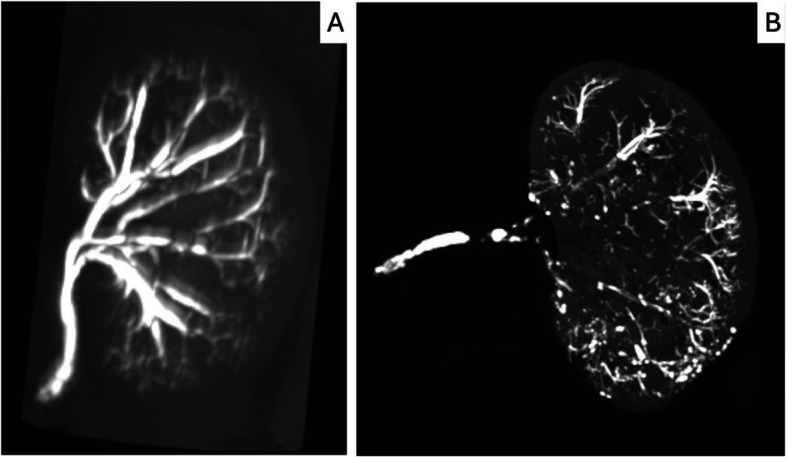

Methods: The left renal arteries of six rabbits were embolized with 12.5% or 25% Glubran®2. In-vivo micro-CT scans were performed immediately after embolisation (M0) and ex-vivo scans and a histological assessment were done at one month (M1). Magnetic resonance imaging (MRI) was done at M1 to assess arterial occlusion and parenchymal changes. Quantitative and semi-quantitative parameters reflecting glue distribution, cast integrity, and tissue response were analysed. Statistical comparisons used non-parametric tests.

Results: All six embolisations were completed without complications. Micro-CT at M1 revealed significant cast resorption and fragmentation with both concentrations, but with no evidence of arterial recanalization. MRI and histology confirmed the persistent vascular occlusion with chronic ischemic changes in the renal parenchyma. Compensatory neovascularization from the renal capsule was observed, with no significant differences in histological inflammation between the two concentrations. Glue casts remained within the arterial lumens and were often surrounded by granulomatous inflammation.

Conclusions: Glubran®2 was effective for renal artery embolisation, even at a low concentration of 12.5%: despite partial cast resorption, the arteries remained occluded. Micro-CT proved to be a powerful tool for assessing changes in glue casts. Longer-term studies are warranted to further assess vascular remodelling and occlusion durability.